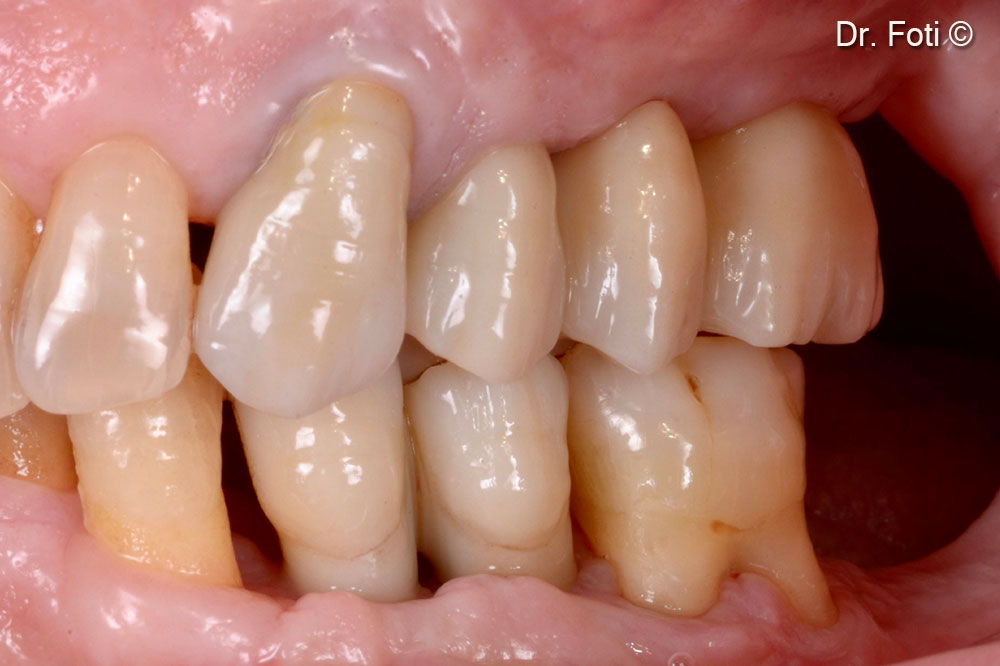

Prosthetic rehabilitation using a screwed monolithic zirconium bridge. Papillae are absent, but there is adequate keratinised mucosa